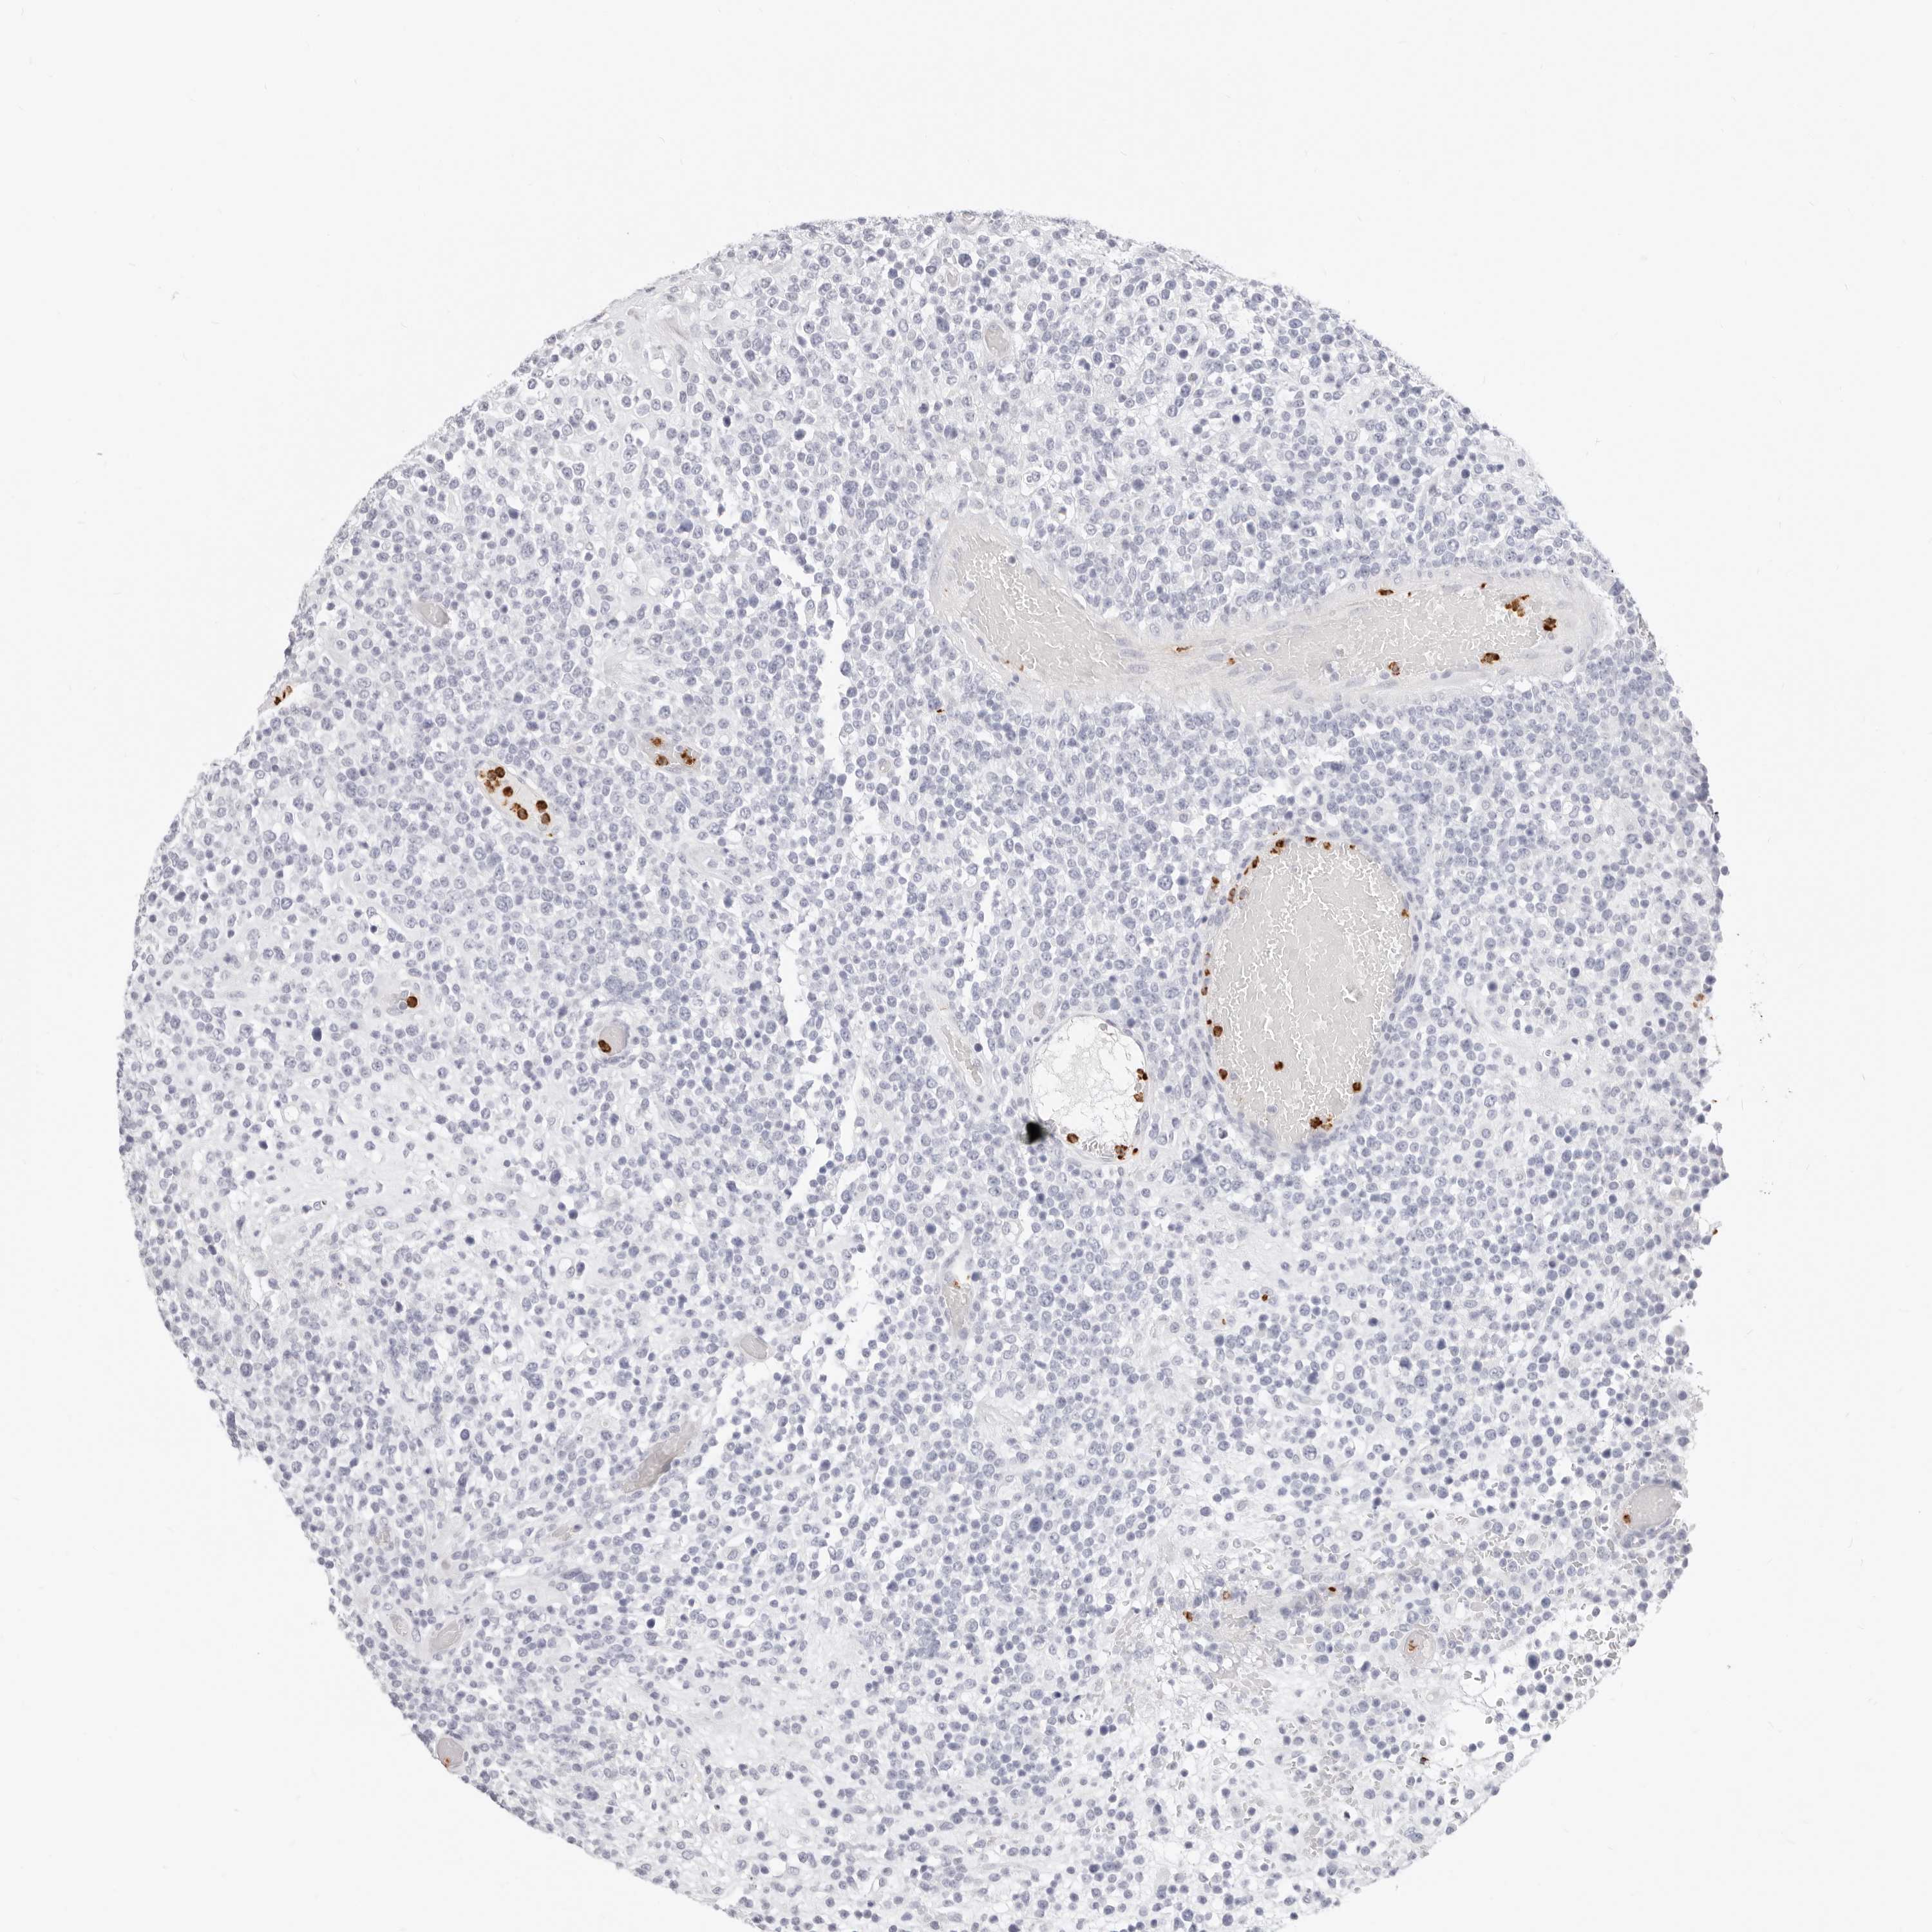

LYMPHOMA - Protein expressioni

A mouse-over function shows sample information and annotation data. Click on an image to view it in a full screen mode. Samples can be filtered based on level of antibody staining by selecting one or several of the following categories: high, medium, low and not detected. The assay and annotation is described here.

Each image is clickable and will lead to virtual microscopy that enables deeper exploration of all samples and also displays staining intensity scores, fraction scores and subcellular localization as well as patient and tissue information for each sample.

Antibody CAB015949

Hodgkin's disease, NOS

Malignant lymphoma, non-Hodgkin's type, High grade

Malignant lymphoma, non-Hodgkin's type, Low grade